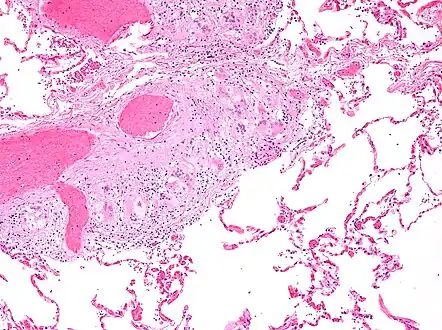

Histopathology

Sarcoidosis is characterized by the formation of non-necrotizing ("non-caseating") granulomas in various organs and tissues.[96] Giant cells, specifically Langhans giant cells, are often seen in sarcoidosis.[97] Schaumann bodies seen in sarcoidosis are calcium and protein inclusions inside of giant cells as part of a granuloma.[98] Asteroid bodies can be seen in sarcoidosis.[98] Hamazaki–Wesenberg bodies can be seen in lymph nodes and more rarely in lung biopsies with sarcoidosis and are inclusion bodies of lysosomes with protein, glycoprotein and iron.[99]

_lymph_node_biopsy.jpg.webp) Sarcoidosis in a lymph node

Sarcoidosis in a lymph node